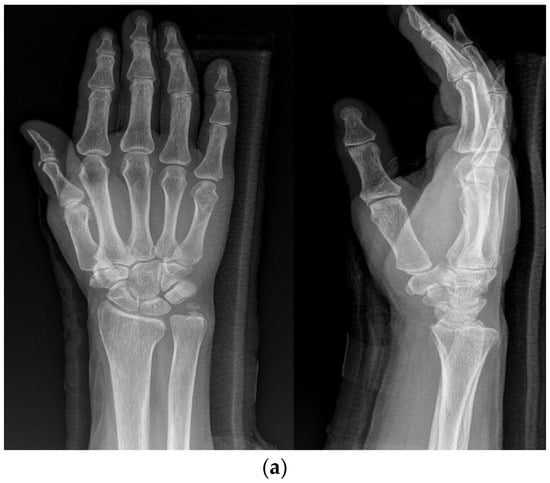

The KP method involved the insertion of two K-wires across the fracture site to stabilize the fracture. The number and size of K-wires used were determined based on the surgeon’s preference and the specific characteristics of the fracture (Figure 1a,b).

(a) Radiograph of a 70-year-old female patient with displaced little-finger metacarpal neck fracture of the left hand. (b) Radiograph of a 70-year-old female patient who underwent the KP method using two K-wires.